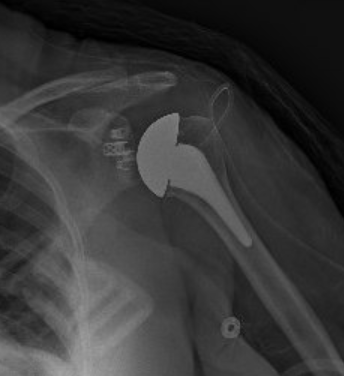

BH is a right hand dominant 70-year-old female, who is retired and moderately active. She presents with 8 months of progressively worsening left shoulder pain affecting her ADLS, sleep and recreational activities. She is 10 years s/p a right anatomic total shoulder arthroplasty. Radiographs and advanced imaging reveal glenohumeral joint advanced degenerative joint disease with an intact rotator cuff. Preoperative planning reveals a native 3 degrees of retroversion with 0 degrees of inclination. As she was extremely happy with the fully functional contralateral shoulder she has enjoyed for the past decade, she was interested in the same solution – an anatomic total shoulder arthroplasty.

At age 70 secondary rotator cuff tears following anatomic total shoulder arthroplasty must be weighed against complications and postoperative function of reverse shoulder arthroplasty [3]. Exactech Predict+ was able to demonstrate comparable postoperative function, scores, pain, and complications. A decision was reached to proceed successfully with an anatomic total shoulder arthroplasty.